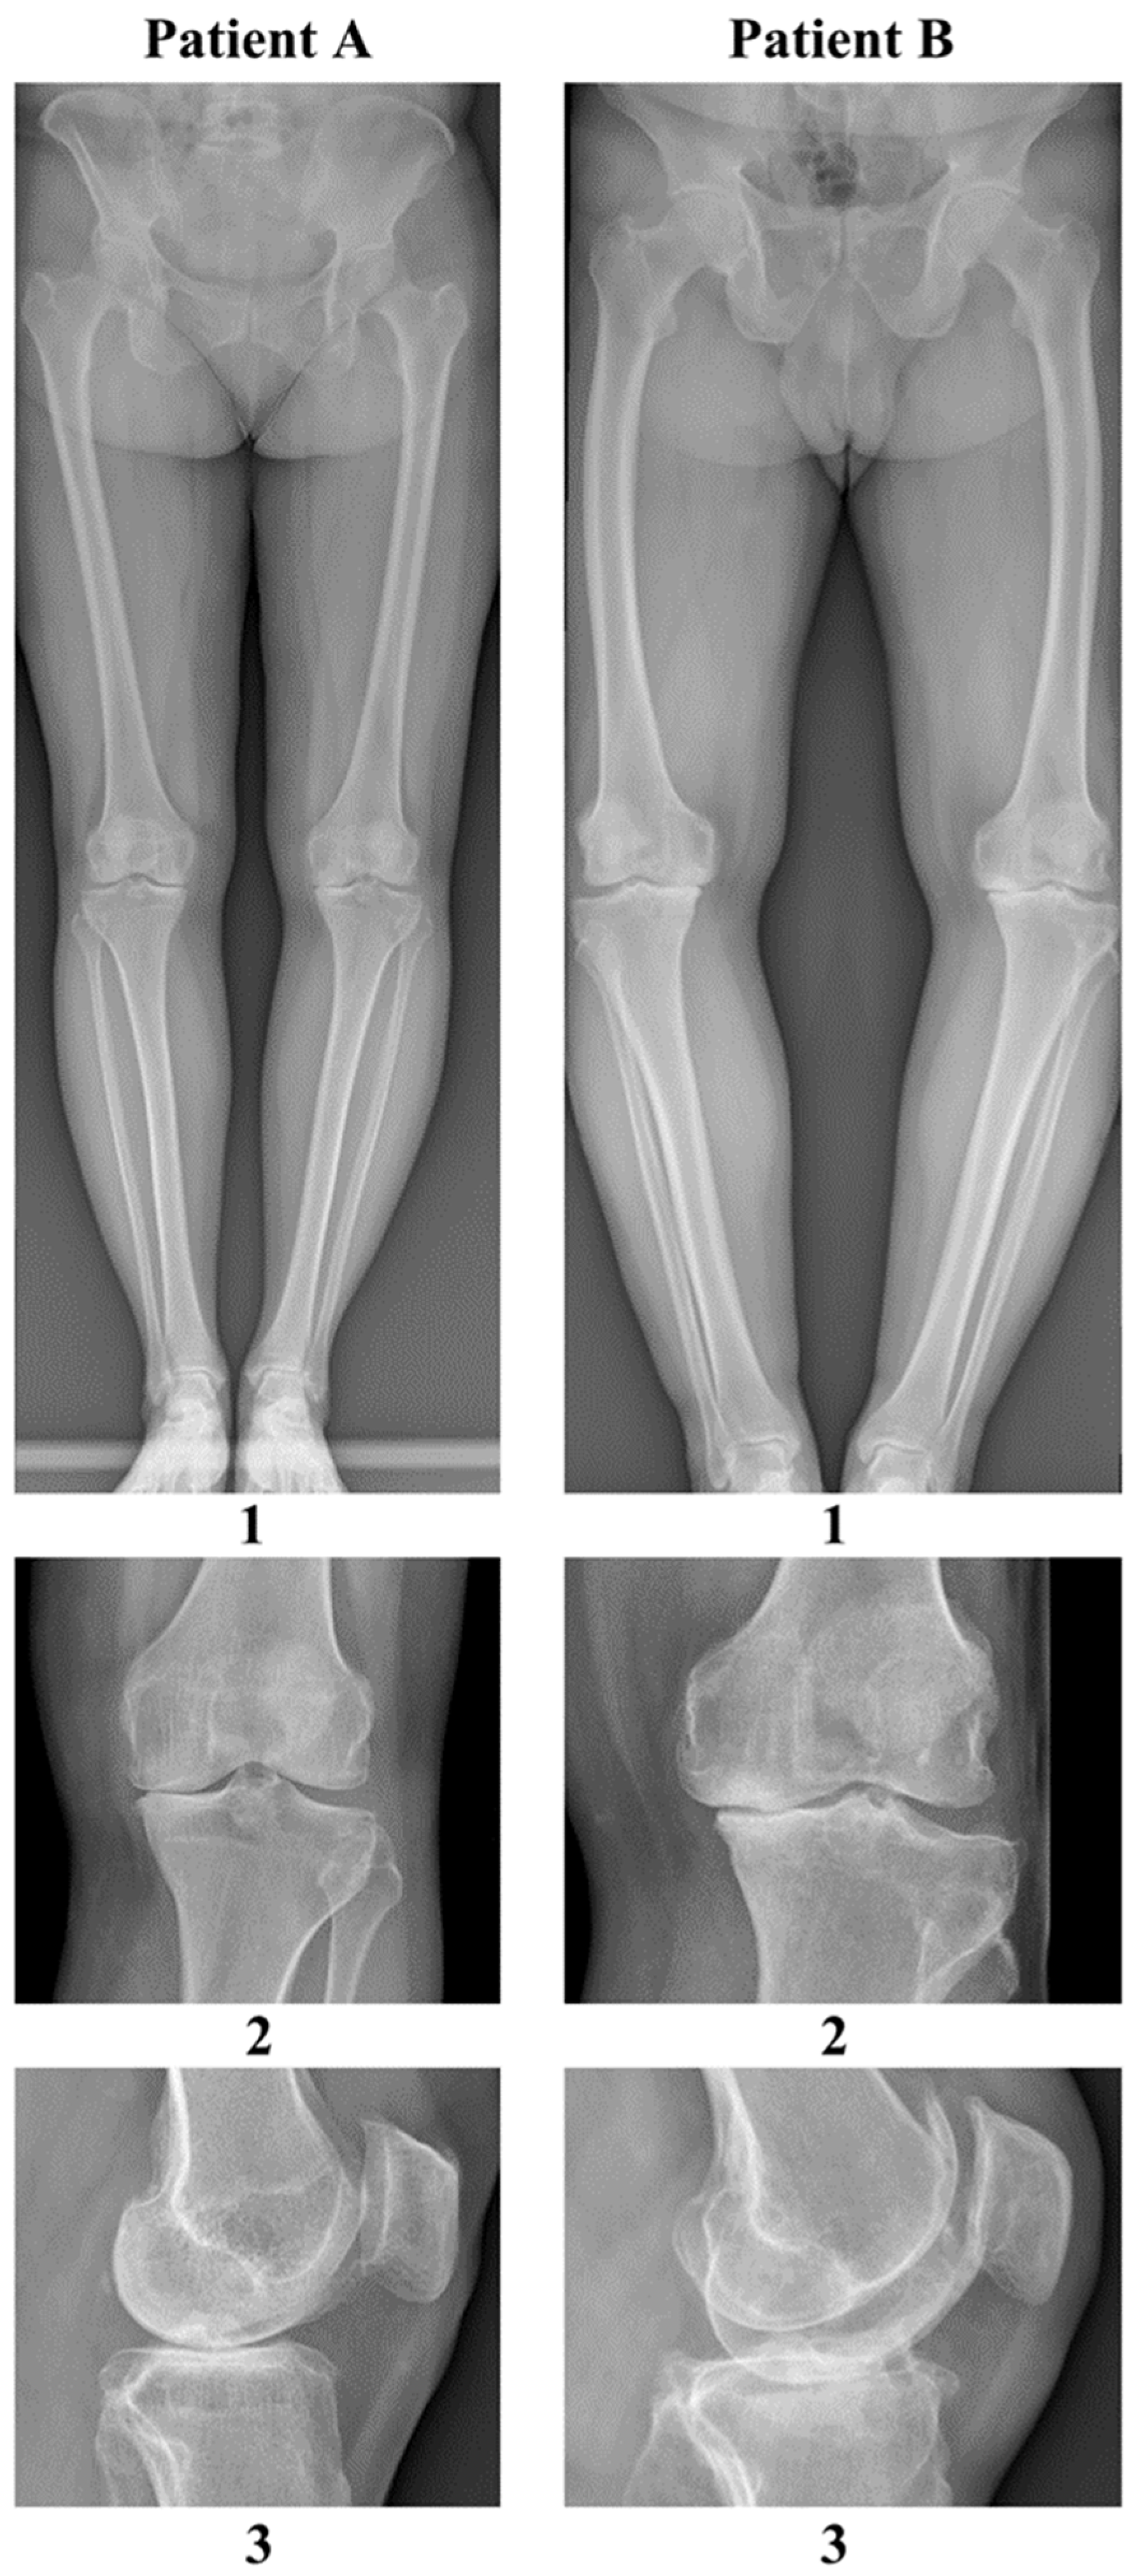

| Feature | Patient A | Patient B |

|---|---|---|

| Gender | female | male |

| Height | 165 cm | 170 cm |

| Weight | 77 kg | 96 kg |

| BMI | 28.0 kg/m2 | 33.6 kg/m2 |

| Blood type | A Rh (−) (no antibodies) | B Rh (+) (no antibodies) |

| Age | 69 | 61 |

| ASA scale | 2 | 2 |

| Occupation | office worker | farmer (farm work, contact with domesticated ruminants) |

| Chronic diseases | hypertension overweight restless legs syndrome, multilevel spondyloarthritis positive tuberculin skin test during childhood | hypertension, obesity class 1, recurrent urinary tract infections, during childhood |

| Chronic medications | ropinirole rosuvastatin lacidipine, valsartan mianserin, paracetamol + tramadol | amlodipine + telmisartan acetylsalicylic acid potassium aspartate magnesium aspartate |

| Previous surgeries and procedures | tonsillectomy (age 15) appendectomy (age 16) ovarian cyst removal (age 46) dental prosthetic implantation (age 64) decompression of stenosis in the lumbar spine (age 68) | right-sided inguinal hernia (age 58) |

| Allergies | none | household dust trimethoprim–sulfamethoxazole |